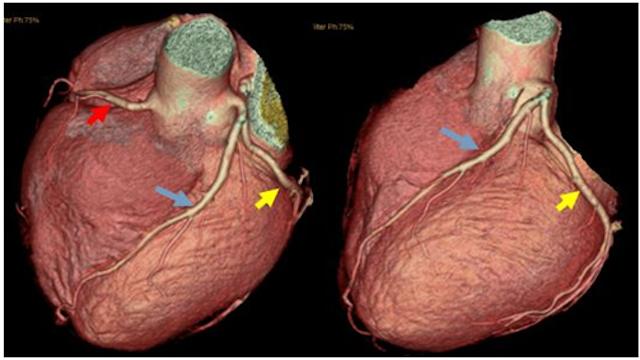

64列CTの誕生と動的追跡技術の開発により、非侵襲的な方法で心臓の血管を検査し、冠動脈の狭窄の有無と程度を特定することができるようになった。この技術は、針や手術室を怖がる胸部圧迫感や胸痛のある多くの患者に役立っている。この検査の主な原理は、造影剤を静脈内に注射し、造影剤で満たされた冠動脈をCTでらせん状にスキャンすることです。 その後、冠動脈の各スキャンスライスを画像結合技術で結合して冠動脈の画像を形成します。

この検査は非侵襲的で安全ですが、いくつかの欠点があります、①リズムコントロール64列CTは心拍数を60拍/分以下にコントロールする必要があり、より速い128列とデュアルソースCTも心拍数を70拍/分以下に可能な限りコントロールする必要があります。この文章を覚えて、もし冠状動脈CT検査で冠状動脈性心臓病ではないと言われたら、この文章の信憑性は99%に高いが、もし冠状動脈CT検査で冠状動脈性心臓病と言われたら、この文章の信憑性は70%しかない。

3、冠動脈CT:表在静脈から造影剤を注入し、CT撮影を行うので、直接動脈造影より安全性が高いが、画像を合成するため、心臓のリズムに一定の条件があり、診断能力は冠動脈造影より弱い;

5.冠動脈CTA(CT冠動脈造影)ヨード造影剤を血管内に注入する方法である。血管内にヨード造影剤を注入し、CT(コンピュータ断層撮影)で冠動脈を見て、奇形や心筋のブリッジ、冠動脈のプラークや狭窄の有無を確認するものです。この方法の利点は「非侵襲的」であり、冠動脈にカテーテルを挿入する必要がないことである。しかし、X線なので石灰化を見るには良いのですが、狭窄を見るには限界があり、あまり正確ではありませんし(機器や検査者の技量に関係します)、さらに心拍が速かったり、不整脈があると撮影効果にも影響します。したがって、この方法は冠動脈疾患の除外に最適であり、狭窄の診断には正確性に欠ける。また、検査中は80~100mlのヨード造影剤を静脈注射する。第一にアレルギーの可能性があること(皮膚テストで検出されないことがある)、第二に造影剤は腎臓から排泄される必要があり、腎臓へのダメージが大きく、腎障害や腎不全を伴う「造影剤腎症」(造影剤腎症)を発症する患者も少なからずいるため、検査前後に「水分補給」の処置が必要となる。したがって、検査前後の「水分補給」は必要である。

- 冠パルスCTAはジュニア配管工冠動脈CTAは実際にはCT検査の一種で、この種のCTを行う際には、手の静脈から一種の薬剤を注入します。この一種の薬剤が造影剤で、造影剤が冠動脈に流れ込むと、この冠動脈の影が映し出され、冠動脈の閉塞や狭窄の有無を判断することができます。冠動脈の主幹といくつかの太い枝はより明瞭に見えるが、細い枝はあまりよく見えない。

要約すると、冠動脈疾患はこの疾患の総称であり、心筋虚血はこの疾患の病態生理学的変化であり、安定狭心症、不安定狭心症、心筋梗塞はこの疾患の虚血状態の異なる重症度である。心電図、心臓超音波、血液検査はすべて、心筋が虚血や壊死を起こしているかどうかを推測する間接的な手段である。冠動脈CTAと冠動脈造影はどちらも造影剤を用いて冠動脈病変を直接観察するものである。 冠動脈CTAは非侵襲的で、簡便で、比較的安価で、太い冠動脈とその枝を観察することができる。冠動脈造影は侵襲的で、比較的高価で、冠動脈の様々な太い枝や細い枝を観察することができ、冠動脈疾患の診断のゴールドスタンダードであり、重症の冠動脈疾患の場合にはバルーン拡張術やステント植え込み術などの冠動脈インターベンション治療を行うことができる。冠動脈疾患を診断するためのゴールド・スタンダードであり、重度の冠動脈疾患に対してはバルーン拡張術やステント留置術を行うことができる。

冠動脈CTAは血管造影と組み合わせて冠動脈をCT検査する手段で、これによって冠動脈疾患を診断することができ、冠動脈プラークの位置、特に石灰化プラークの程度を検査・判断することができる。 また、冠動脈CTAはステントを留置した冠動脈疾患患者のステント部位で血流がスムーズかどうかを評価することができ、同時に胸痛を訴える患者に対して、冠動脈CTA検査によって大動脈、肺、気胸などの問題を発見することができる。胸痛のある患者に対して、冠動脈CTAは大動脈、肺、気胸の問題をスクリーニングするために使用できるが、急性梗塞の問題が強く疑われる患者には推奨されない。

しかし、冠動脈疾患のリスクが高くない一部の人々に対しては、医師は冠動脈CTA技術を用いた冠動脈狭窄のスクリーニングを推奨することがある。冠動脈CTAの精度は冠動脈造影検査にはまだ及ばないが、冠動脈疾患が否定された患者を除外するには十分である。